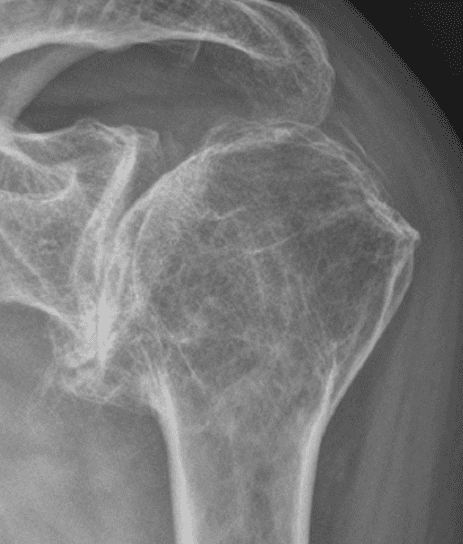

Patient Cases